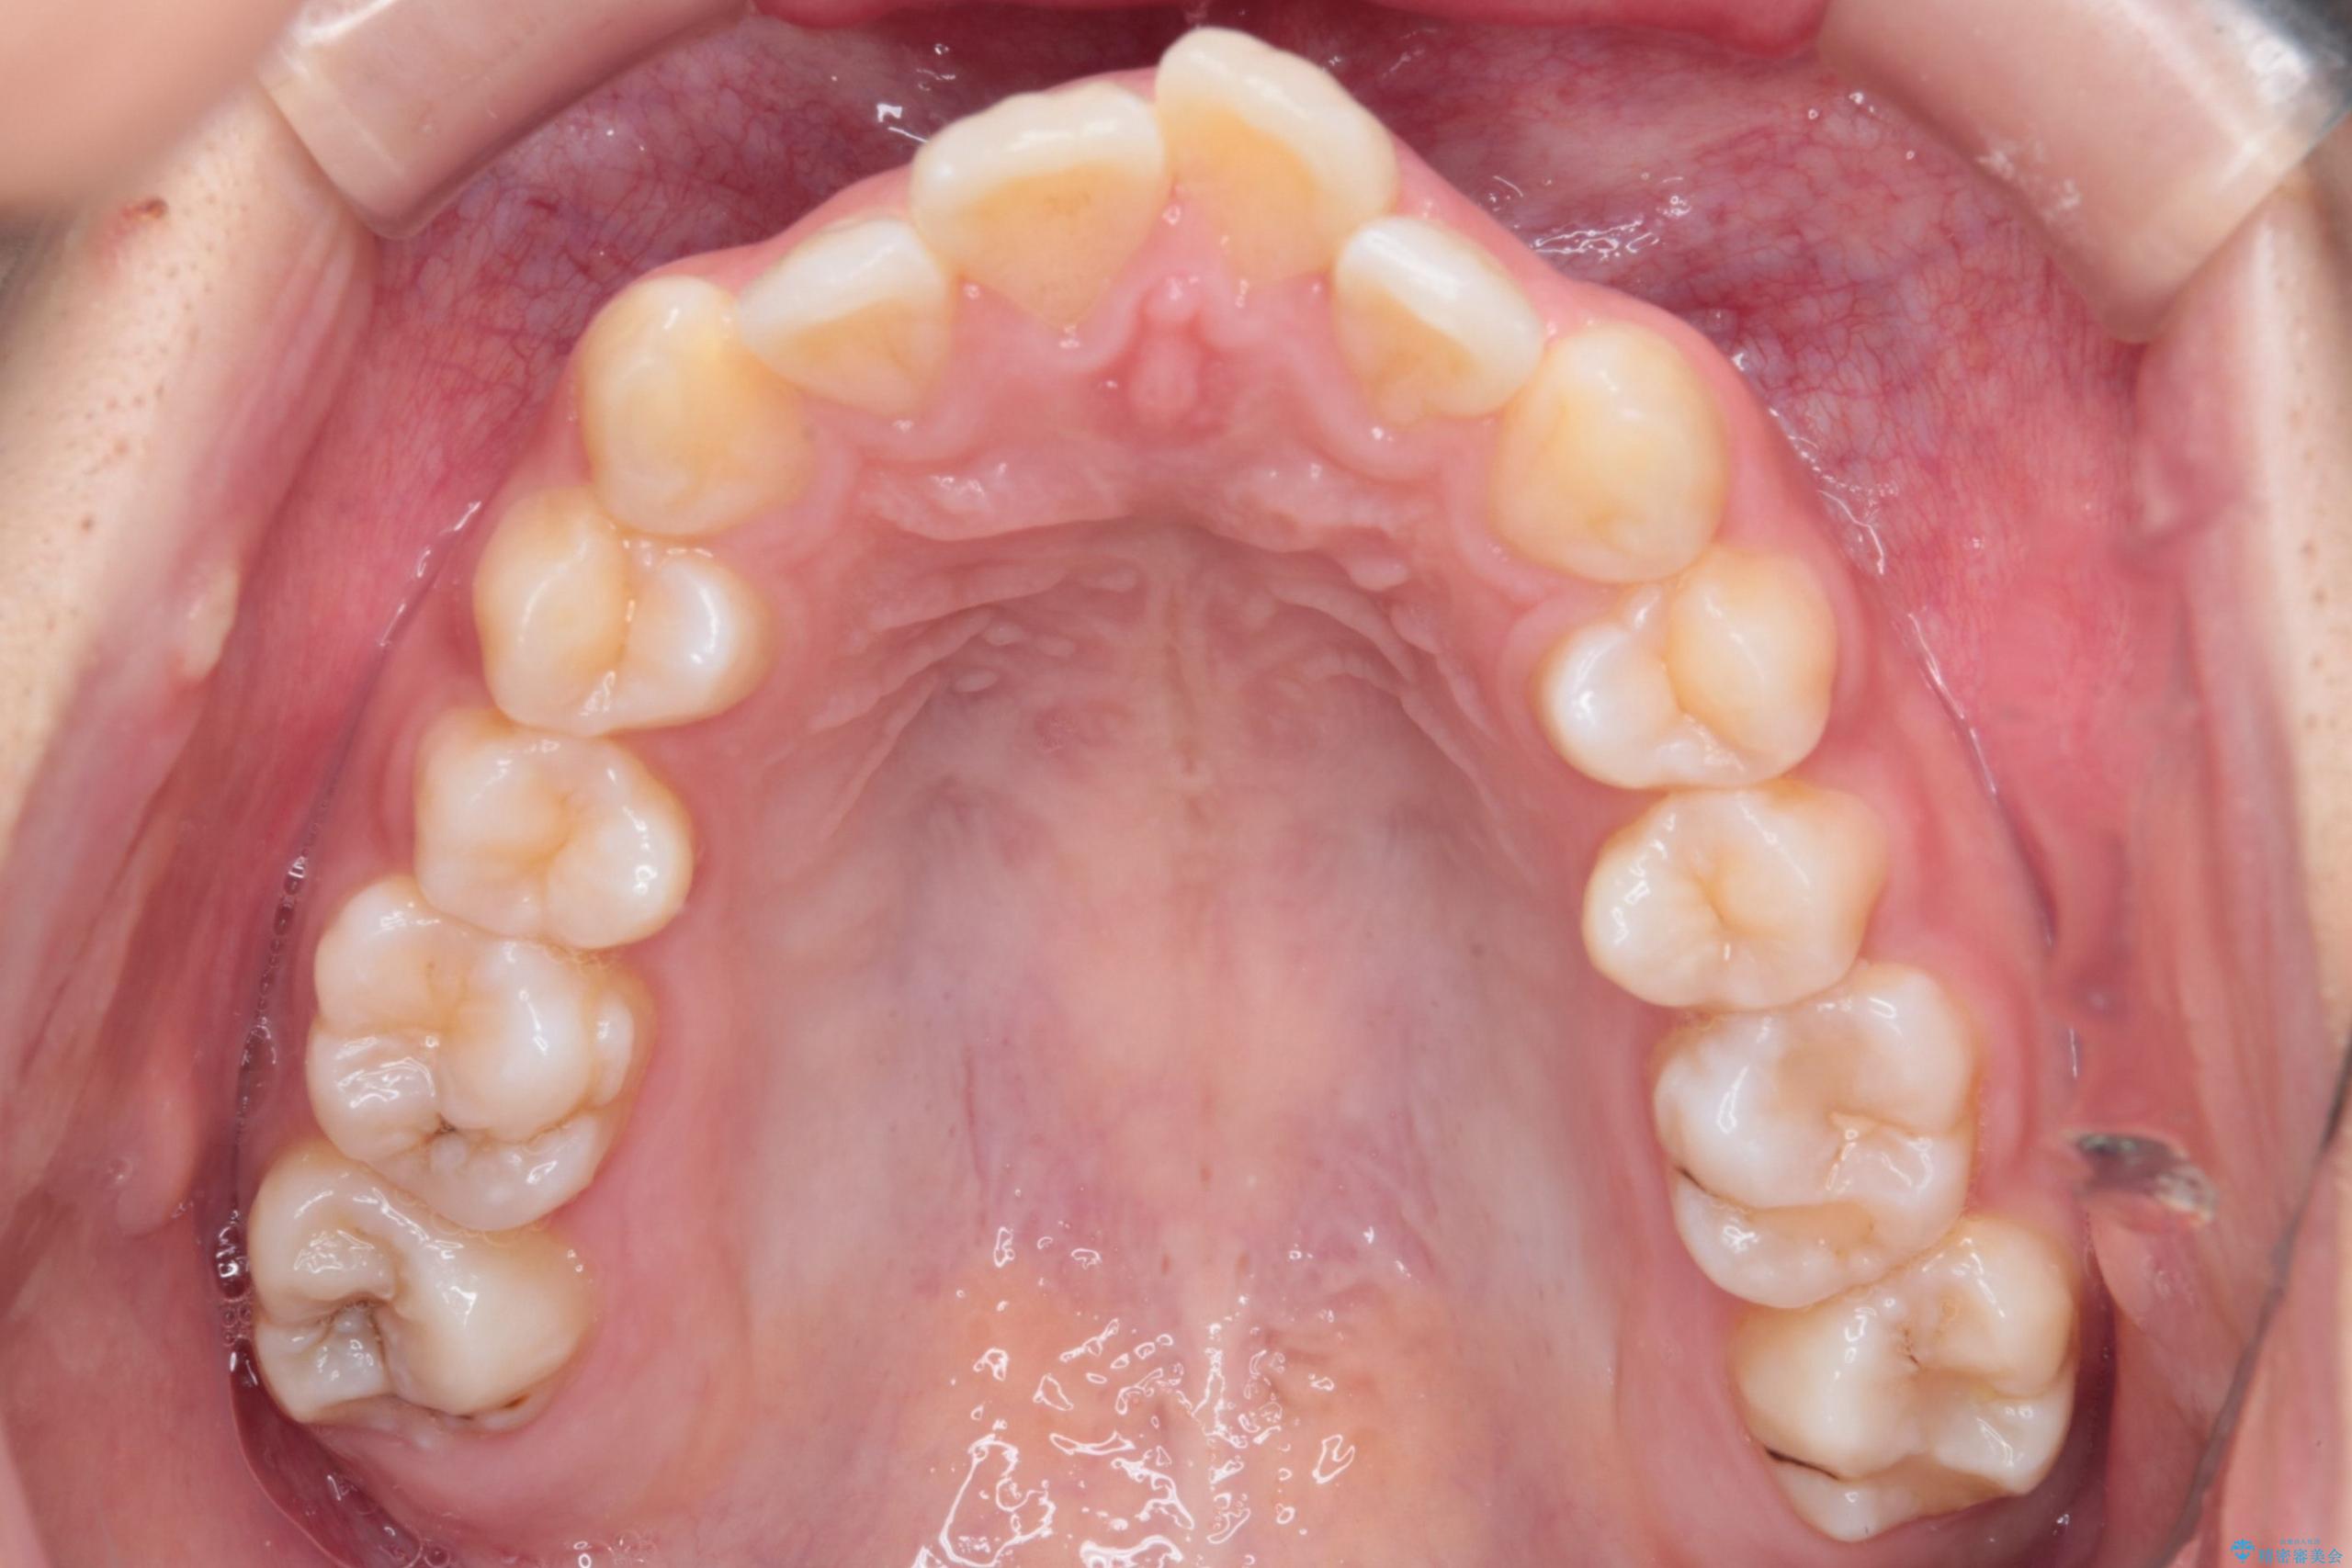

- 前歯から奥歯にかけて歯の重なりが激しい歯のがたつき(重度叢生)を主訴にご来院されました。精密検査の結果、歯が並ぶスペースが大幅に不足しており、歯並びを整え、口元を美しく引っ込めるためには、スペースの確保が必要と診断しました。そこで、上下左右の第一小臼歯(4番目の歯)を計4本抜歯し、そのスペースを利用して歯並び全体を整える抜歯矯正の治療計画を立案。装置には、透明で目立たないインビザラインを採用し、審美性と治療効果の両立を目指しました。

今回の治療では、重度の叢生を改善するため、まず計画通り上下左右4本の小臼歯を抜歯し、歯を並べるための十分なスペースを確保しました。装置には透明で取り外し可能なインビザラインを使用。抜歯によってできたスペースを最大限に活用し、マウスピースを定期的に交換しながら、デコボコを解消しつつ、前歯を効果的に後退させました。

治療の結果、長年の悩みであった重度の歯のがたつきが解消され、口元の突出感も改善。機能的にも安定し、審美的にも美しい、理想的な歯並びを獲得していただけました。